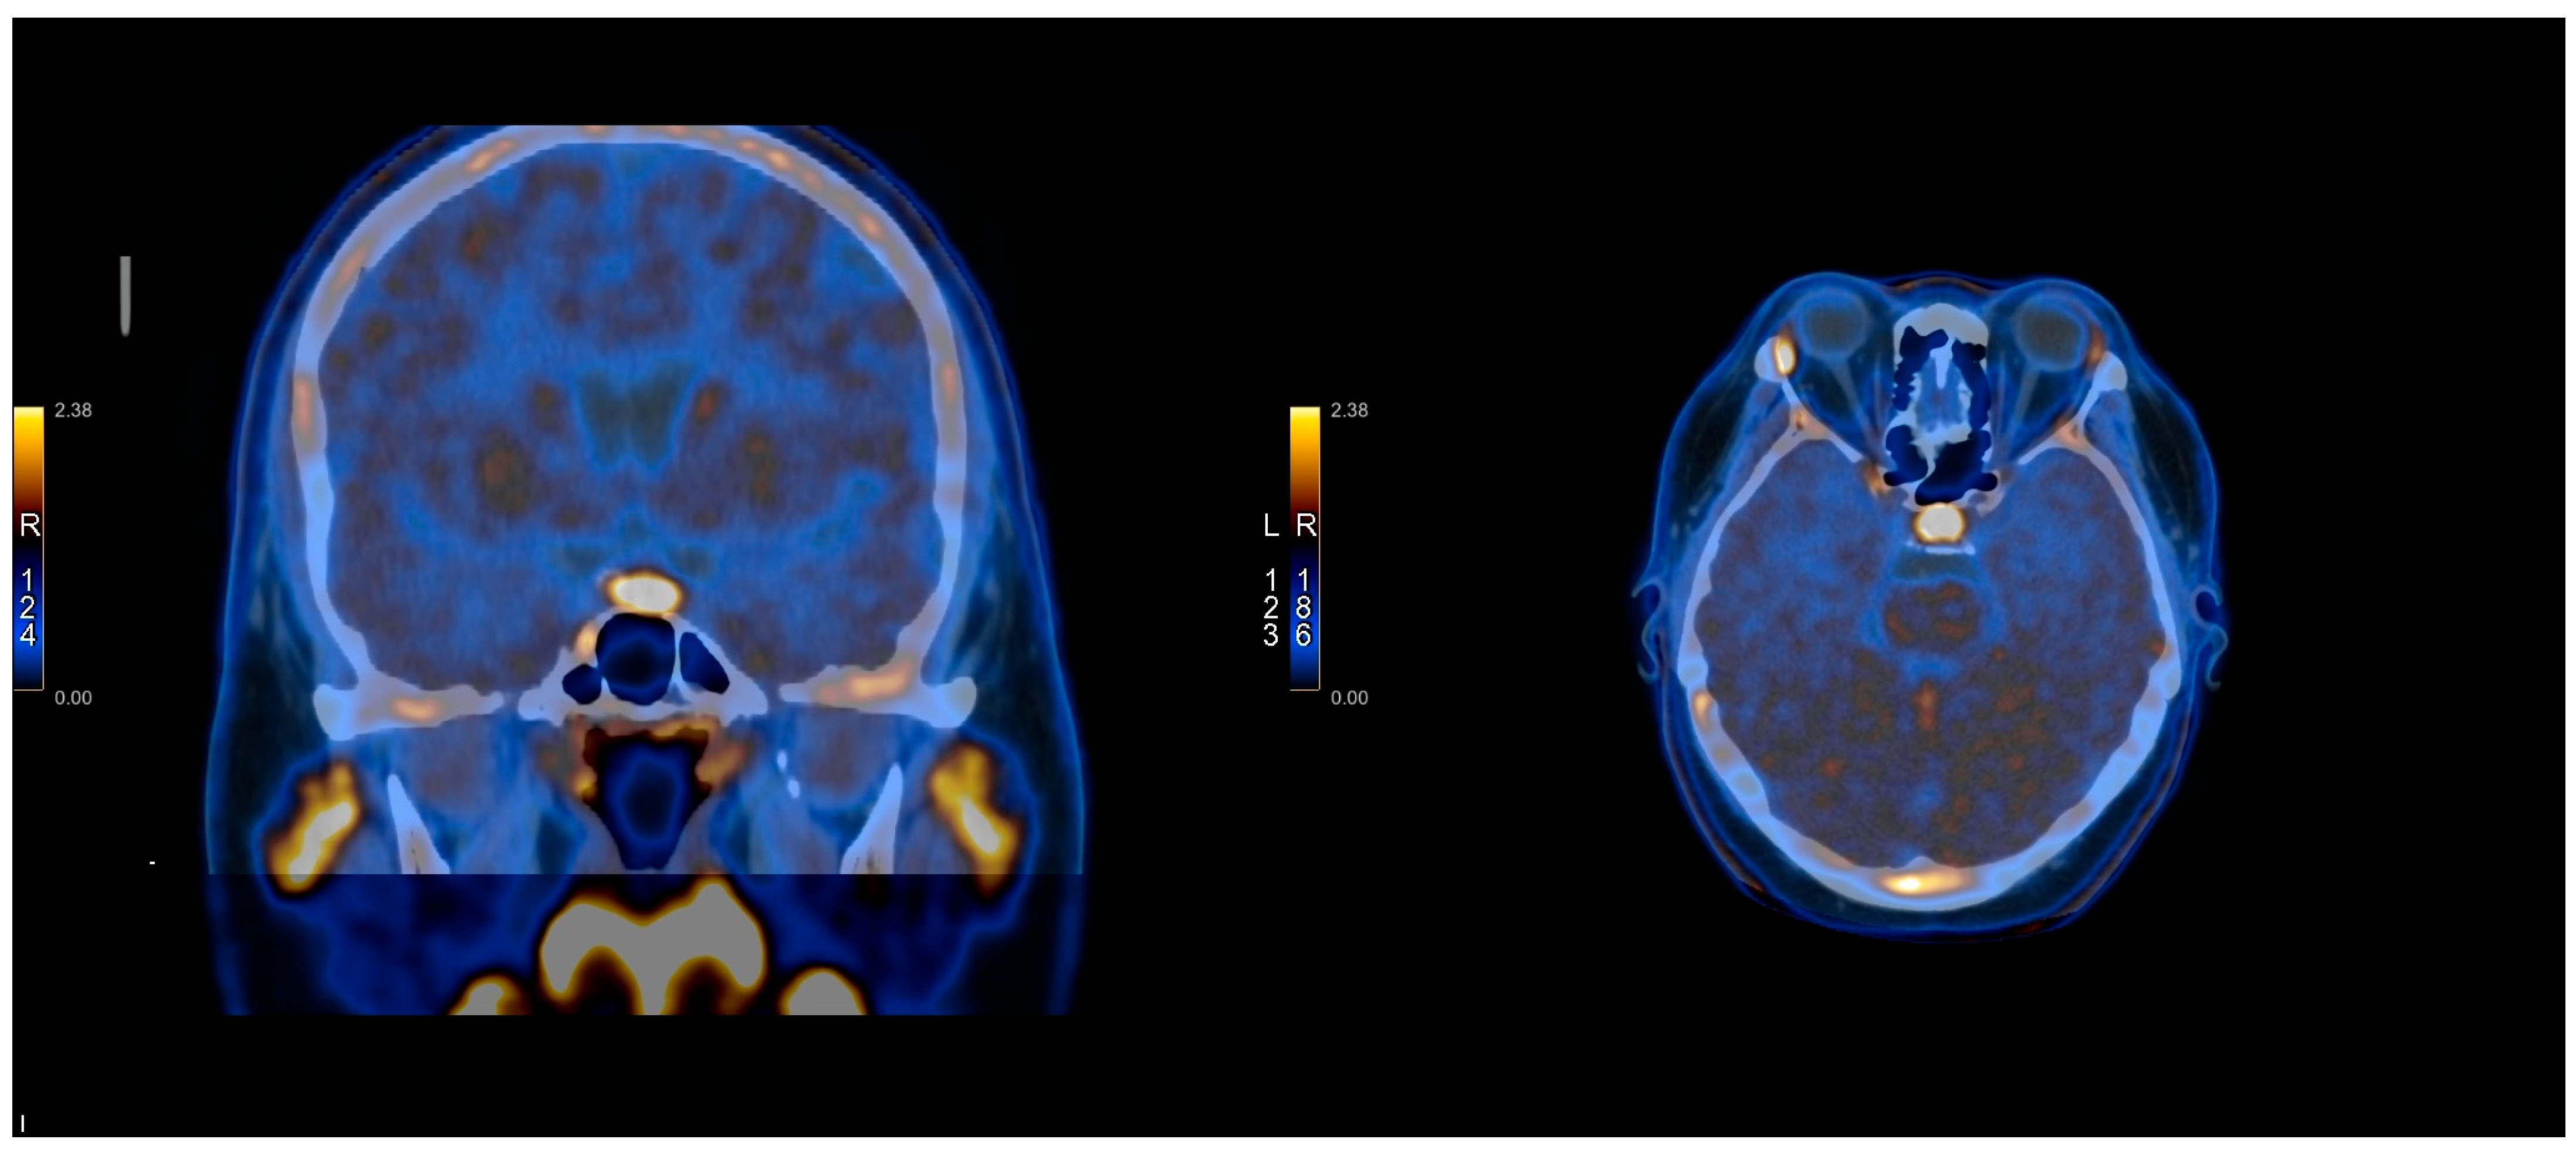

2.3. PET Protocol

2.4. Methionine Protocol